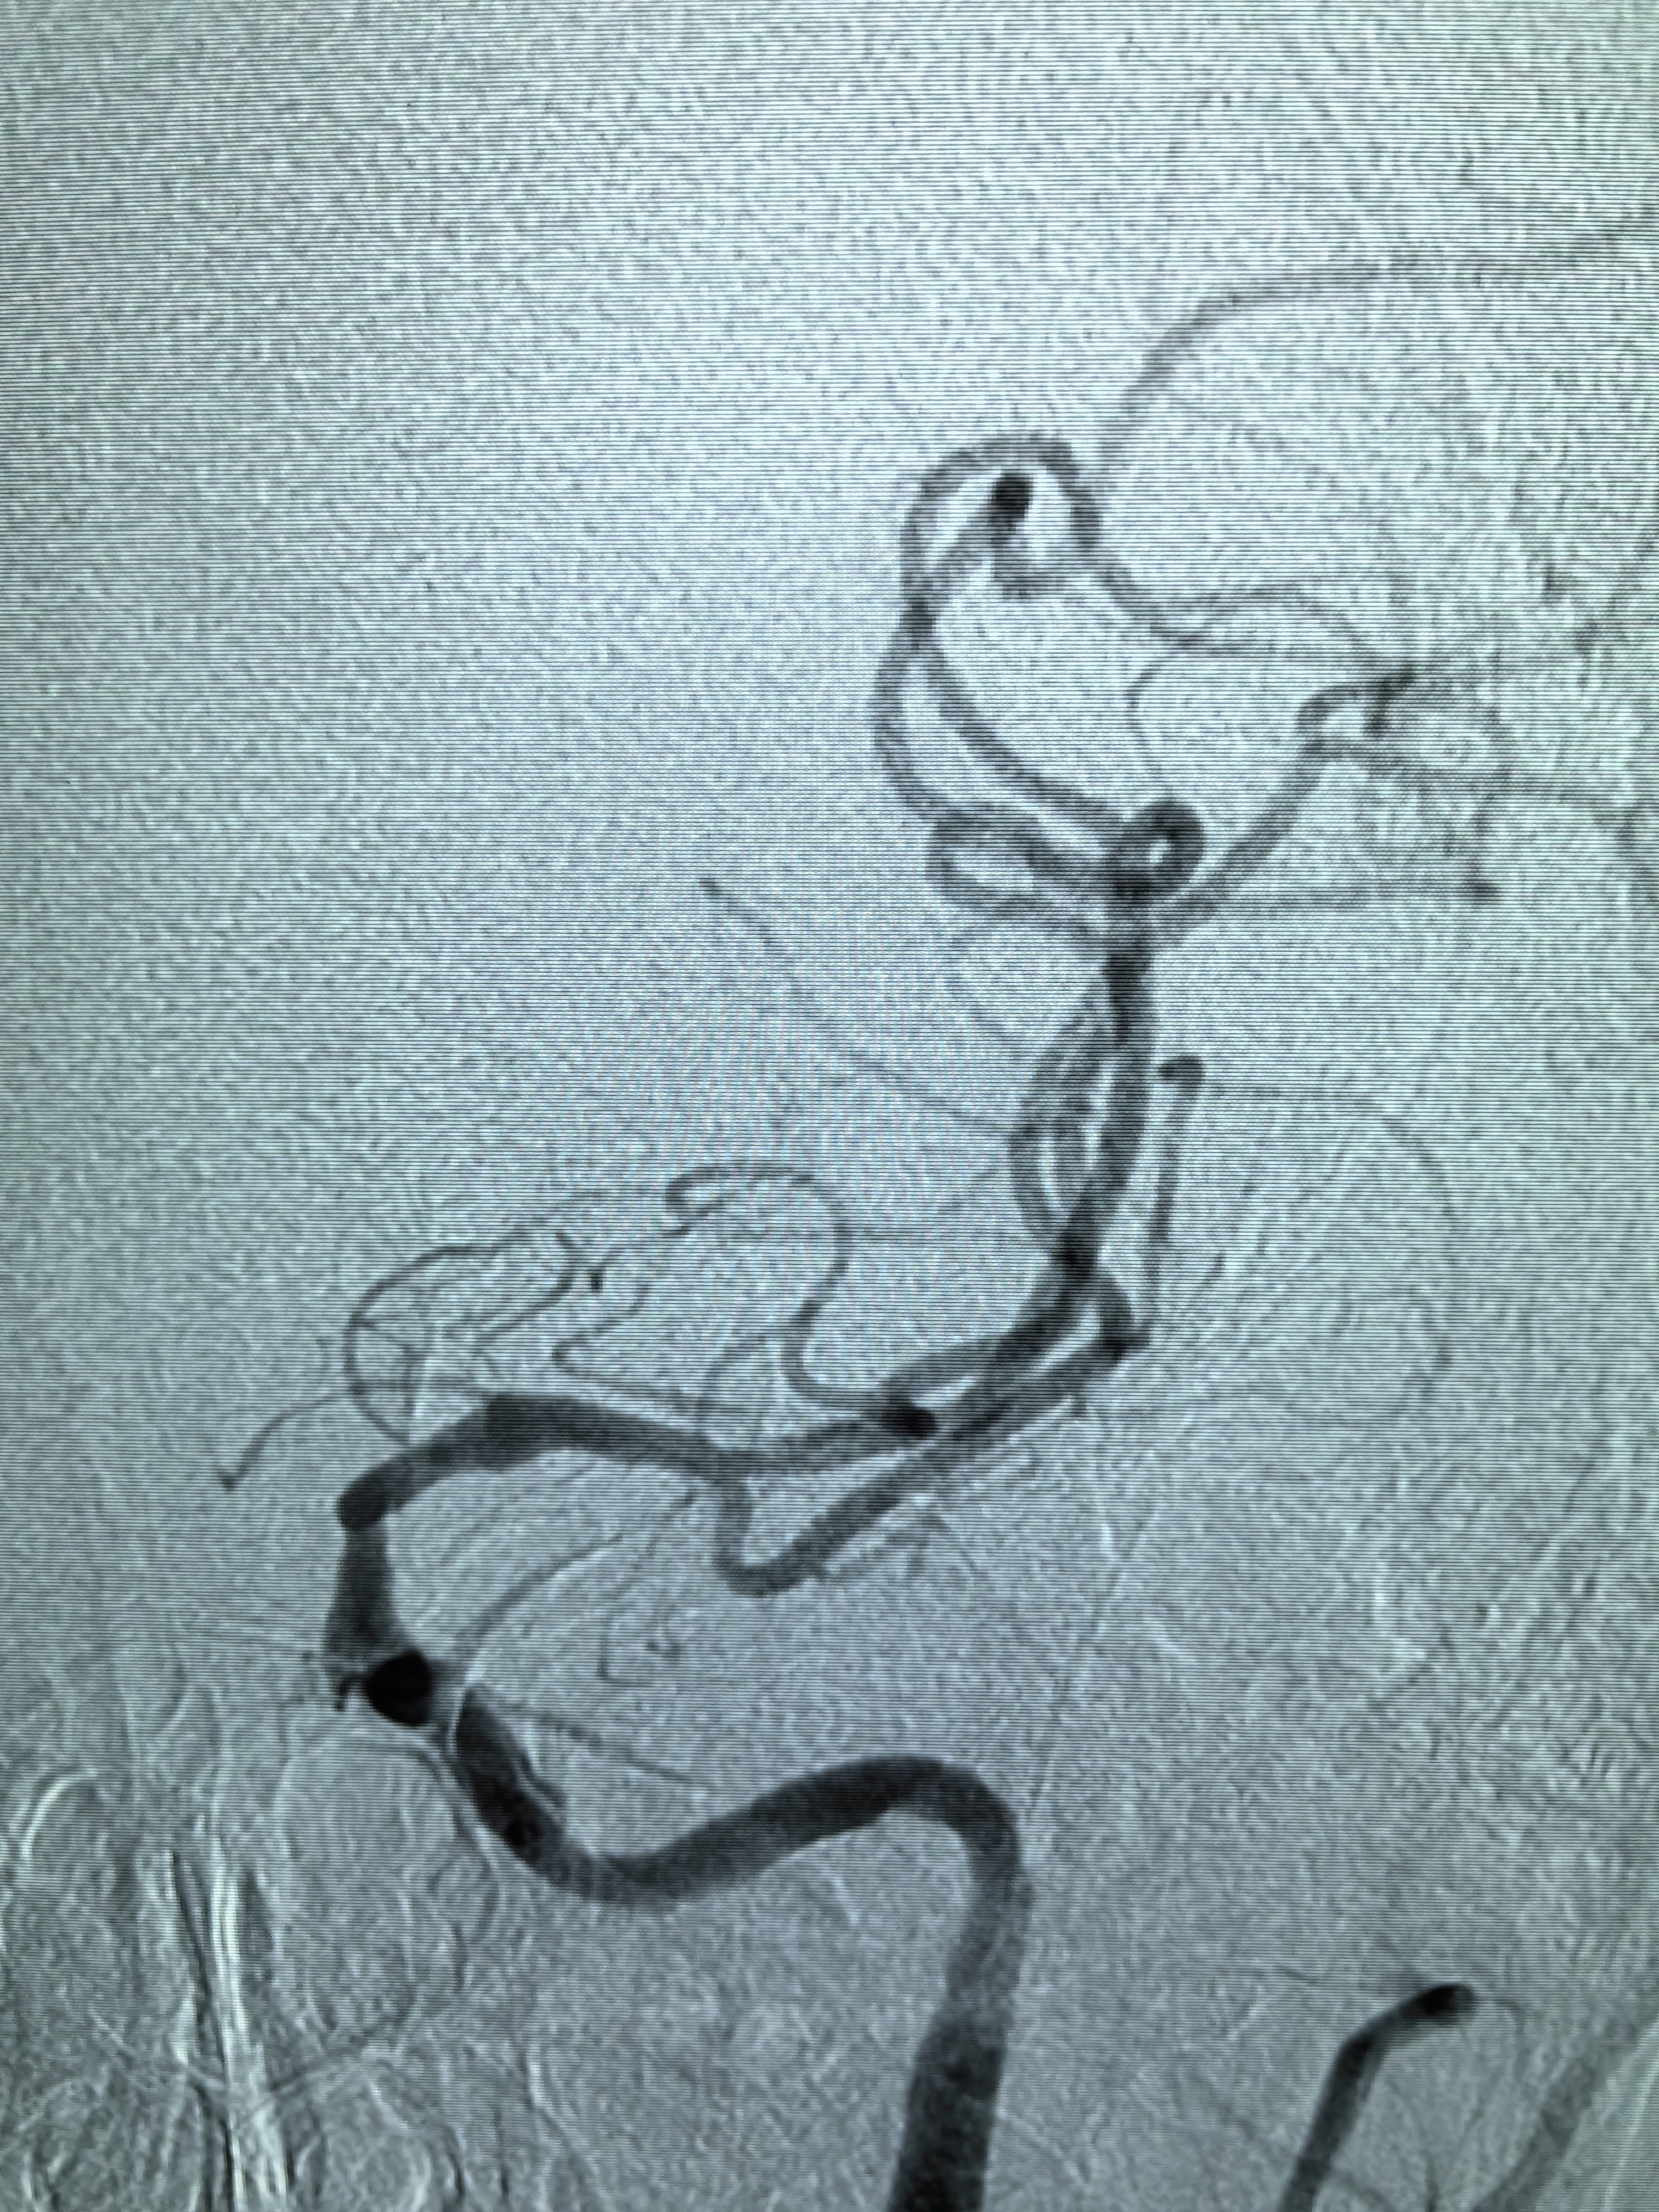

患者男性,70岁,体检发现双侧颈内动脉重度狭窄,1月前行右侧颈内动脉支架成形术,现为治疗左侧颈内动脉狭窄入院。既往高血压病史30年,口服硝苯地平控释片降压,血压控制130/80mmHg。

1、本例患者老年男性,双侧颈内动脉重度狭窄,治疗采取分期处理,间隔4周。

2、左侧颈内动脉从CTA看狭窄合并软斑,具备介入治疗指征。